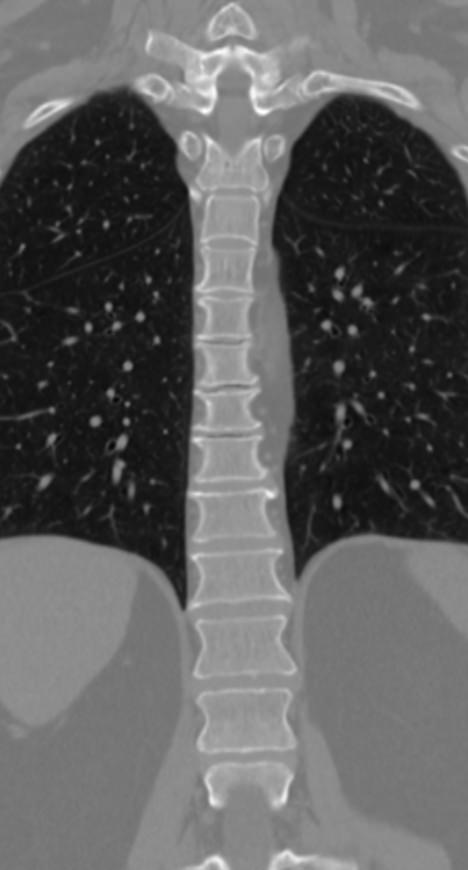

Мультиспиральная компьютерная томография (МСКТ) является современным, высокоинформативным методом диагностики различной патологии позвоночного столба. Благодаря МСКТ можно визуализировать костную структуру позвонков, выявить воспалительные, дегенеративные и опухолевые процессы на исследуемом уровне. В основе метода лежит использование ионизирующего излучения и способность различных тканей по-разному поглощать рентгеновские лучи.

В нашей клинике КТ двух отделов позвоночника проводится на новейших мультиспиральных томографах экспертного уровня TOSHIBA AQUILION (64-срезовый и 128-срезовый). Сканеры производят тончайшие срезы исследуемой зоны толщиной от 0,5 мм и позволяют визуализировать костные структуры позвоночника с высокой детализацией. Увеличенное количество высокочувствительных детекторов аппаратов обеспечивает высокую разрешающую способность и четкость изображений, при этом позволяет выполнить исследование в течение нескольких секунд с минимальной дозой облучения.

Инновационные возможности мультиспиральных томографов, которыми оснащены наши медицинские центры, позволяют создавать 3D-модели позвоночника на рассматриваемом уровне для более точной локализации очага и оценки взаимного расположения органов и тканей.

- патологические изгибы позвоночника, сколиоз, усиленный или выпрямленный лордоз как нарушение статической функции позвоночника;